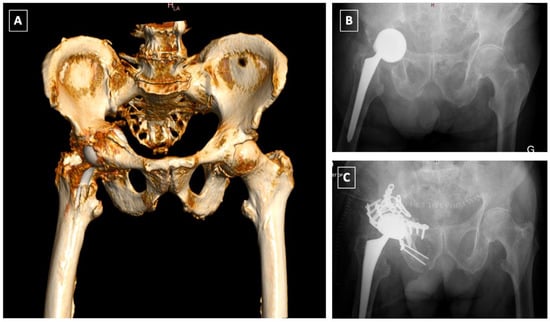

2. Classification of Peri-Prosthetic Acetabular Fractures

3. Diagnosis